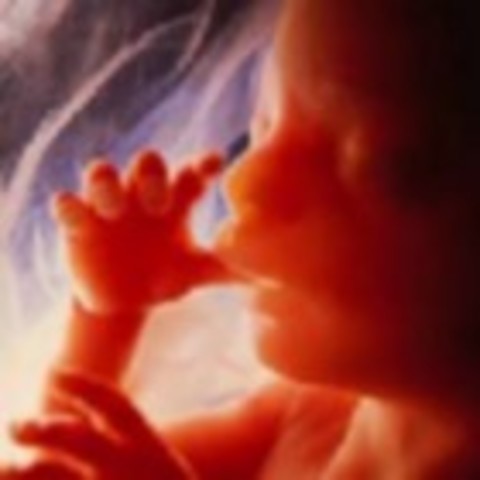

• Week 26 of the Second Trimester

Week 26 of the Second Trimester

The baby will start to suck on his thumb which will stregthen his cheek muscle. This ends the Second Trimester.

Facts:

1)The baby measures 14 inches long and weighs over 1.7 pound.

2)Baby measures 35.5cm long and weighs over 760 grams.